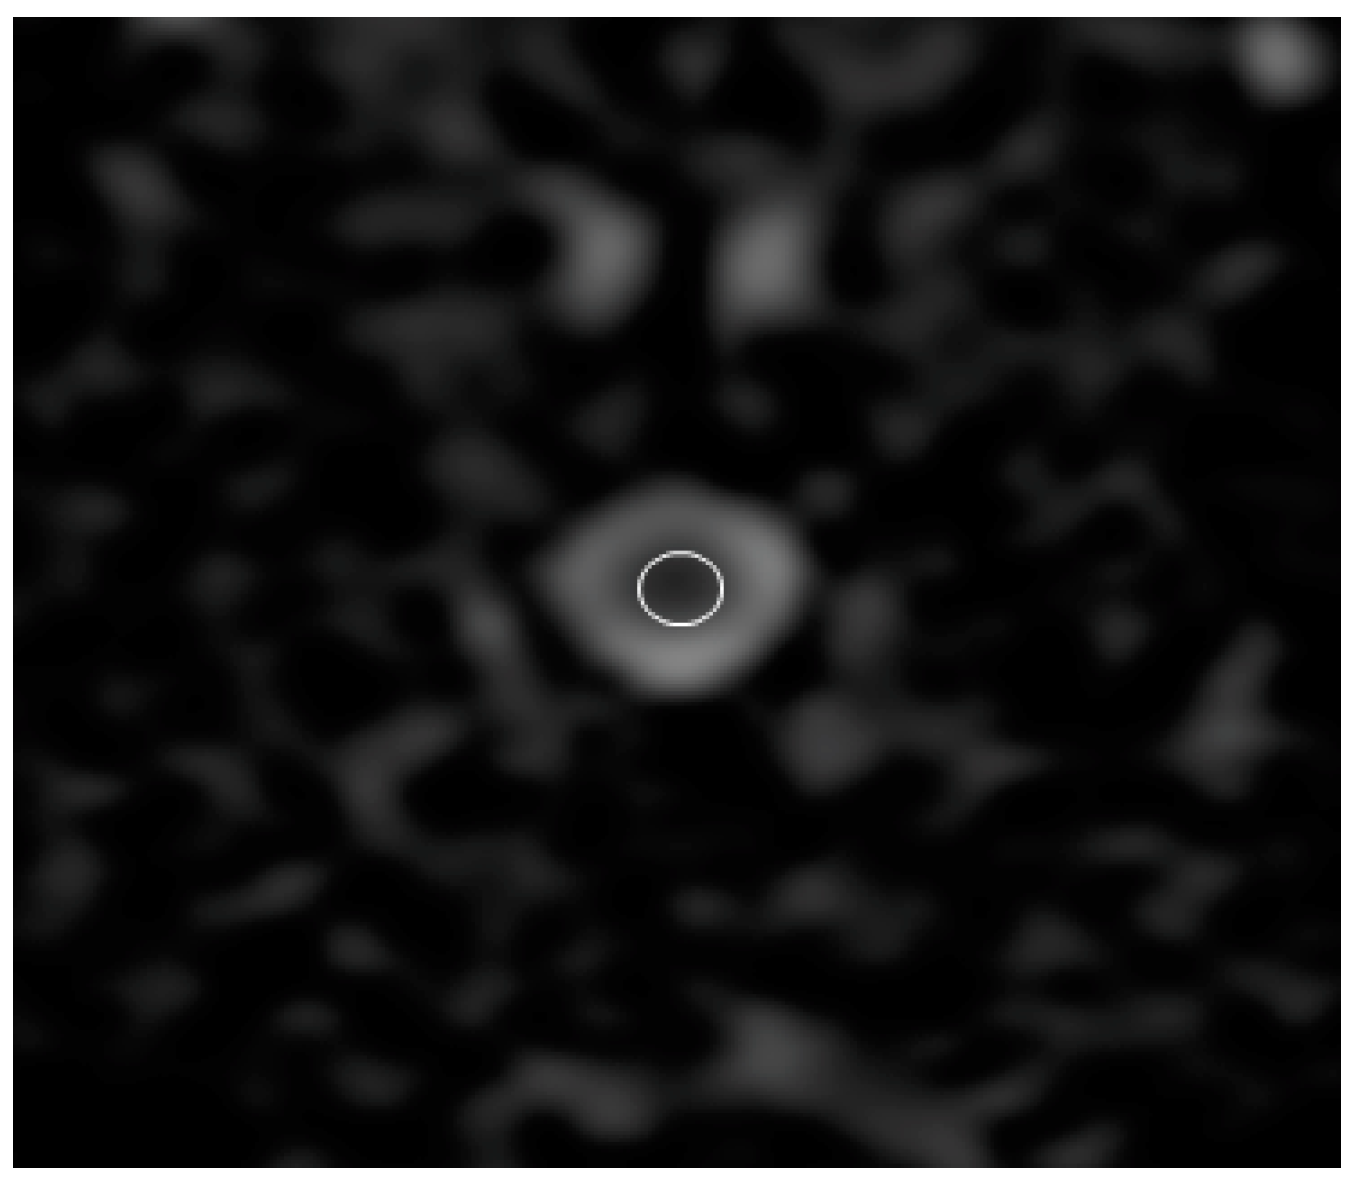

Sagittal T2 images were used to identify the relevant anatomy. ADC, FA, RA, and three types of diffusion eigenvalue (λ1, λ2, and λ3) maps were created using the package built on the MRI system. To measure the ADC, FA, RA, λ1, λ2, and λ3 values, the regions of interest (ROIs) were placed manually on the spinal cord in all transverse images with special care to include the least amount of cerebrospinal fluid (Figure 2). The size of the ROI was standardized to 0.3 cm2. For ADC, FA, RA, λ1, λ2, and λ3 values, these data were analyzed using a workstation built into the MRI system. The λ1, λ2, and λ3 values were used to calculate DTI parameters using the following formula:

Figure 2. Apparent diffusion coefficient image of the C5 vertebra. The region of interest (ROI) is placed manually on the spinal cord with special care to include the least amount of cerebrospinal fluid. ROI size was standardized to 0.3 cm2.